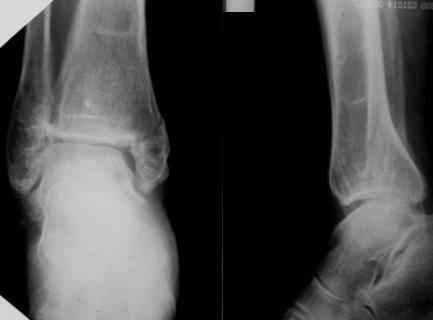

Посмотрели снимки после репозиции - не понравилась зона синдесмоза.

Сделали 3/4-е - впечатление, что в 99-том там что-то было. На

5.11.09г. запланирована КТ.

Косая после репозиции.JPG